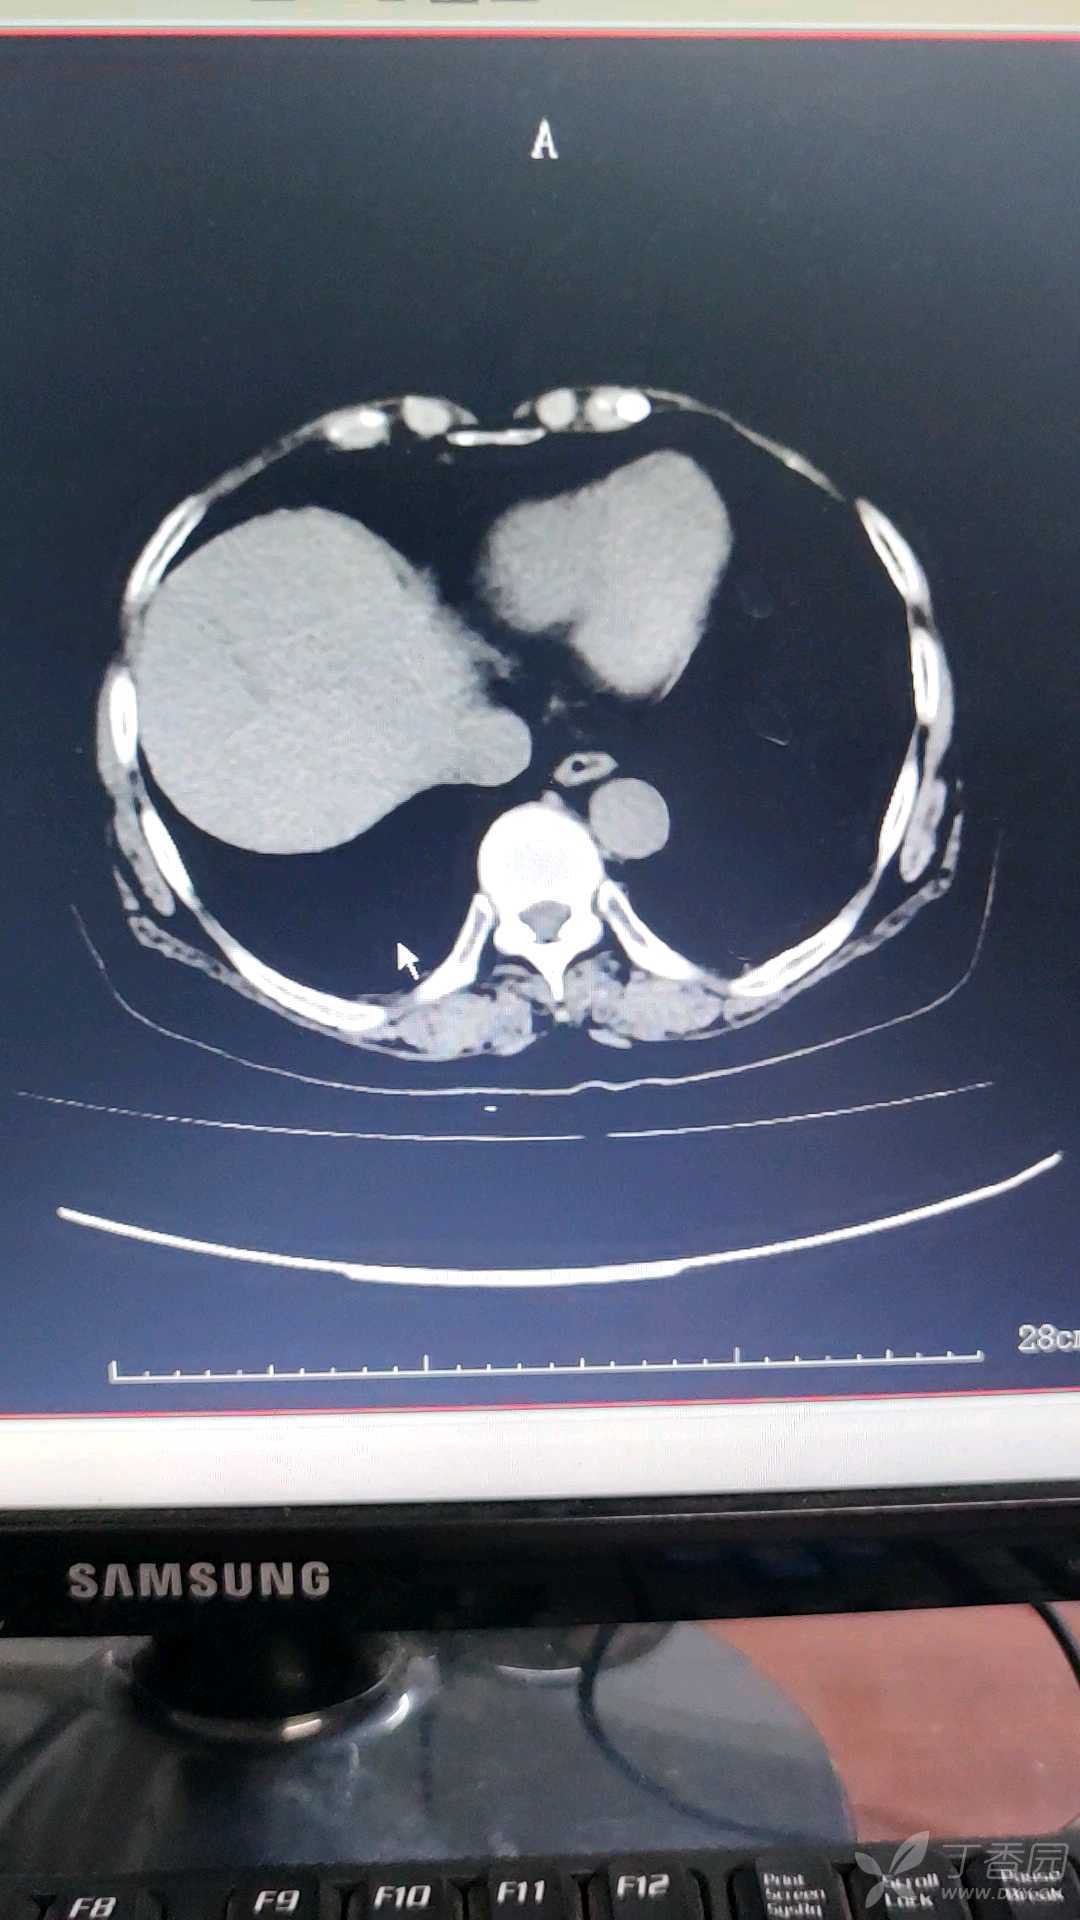

患者女性,74岁,反复下腹部疼痛伴尿频尿急尿痛半年余入院。尿分析白细胞+3,镜检1484,尿培养未见细菌。CT提示双肾多发结石并右肾积水,左肾囊肿,双肾形态欠规则,右侧输尿管积水扩张。予以抗感染治疗可缓解,但易反复。请问考虑是什么原因引起的反复泌尿道感染